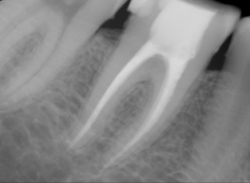

Digi X-Ray, Less Radiation